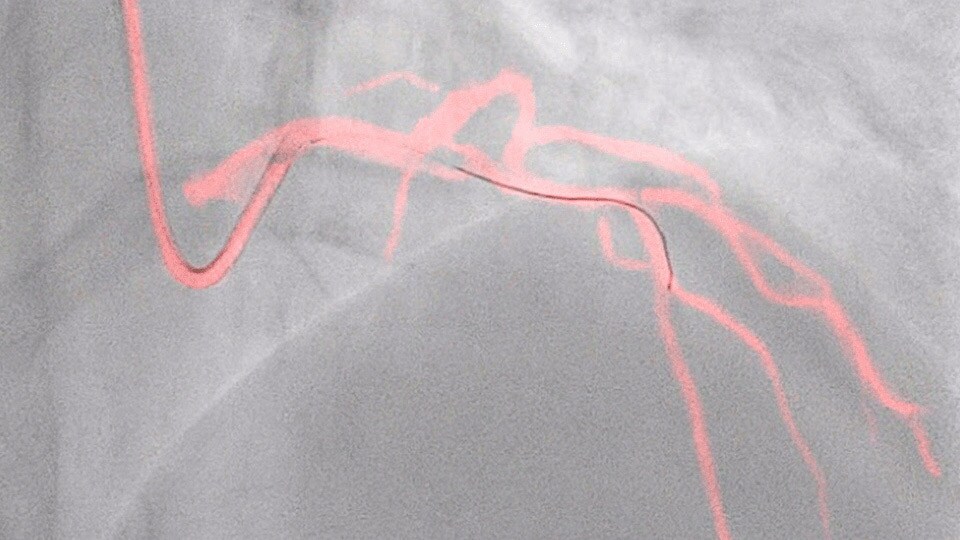

Dynamic Coronary Roadmap

This Philips-exclusive technology provides a real-time view of the coronary arteries and removes the need for additional contrast injections.